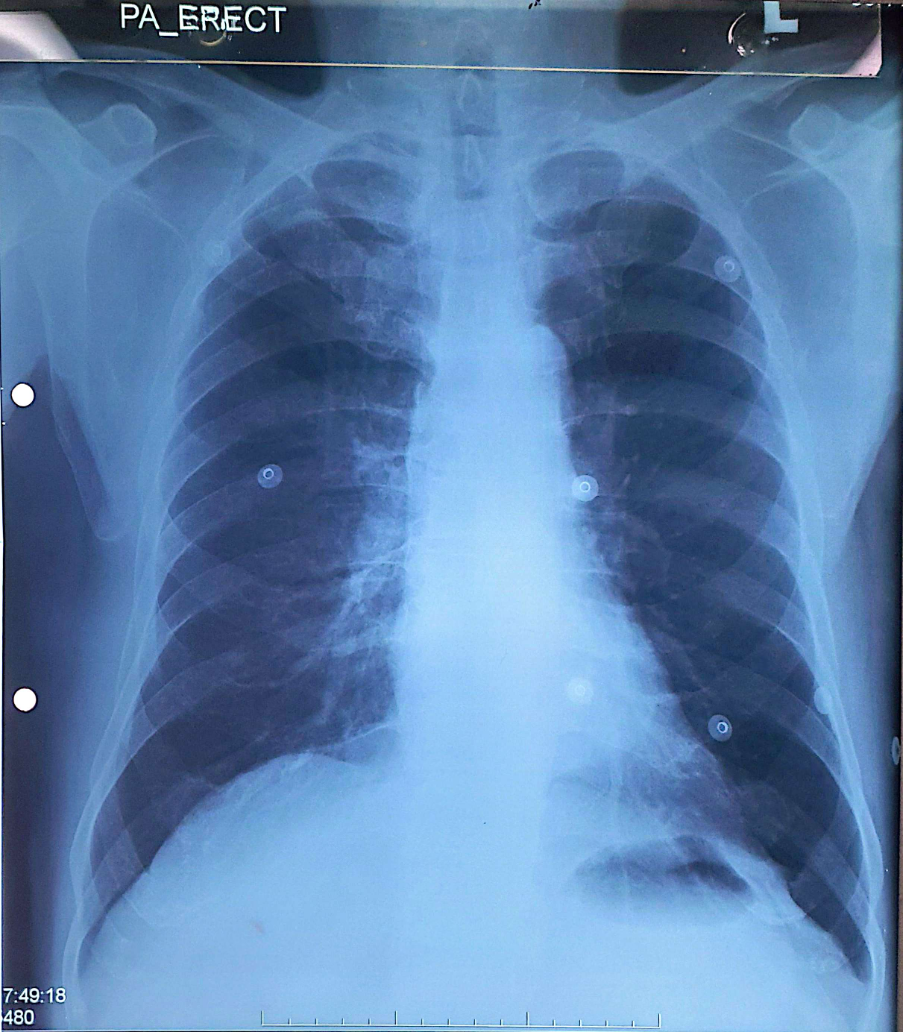

Relevant Test Results Prior to Catheterization

WBC 5.7 x 109/L; Hb 14.5 g/dL; Platelet 269 x 109/LNa 140 mmol/L; K 3.8 mmol/L; Cl 107 mmol/L; Urea 4.4 mmol/L; Creatinine 75 umol/LTroponin I < 3.7 ng/L Creatinine kinase 78 U/L --> 70 U/LECG: sinus rhythm.